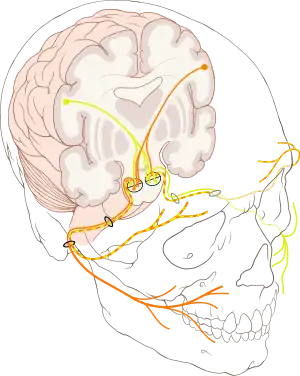

Hemifacial spasm (HFS) is a rare neuromuscular disease characterized by irregular, involuntary muscle contractions (spasms) on one side (hemi-) of the face (-facial).[1] The facial muscles are controlled by the facial nerve (seventh cranial nerve), which originates at the brainstem and exits the skull below the ear where it separates into five main branches.

The first sign of hemifacial spasm is typically muscle movement in the patient's eyelid and around the eye. It can vary in intensity.[6] The intermittent twitching of the eyelid, which can result in forced closure of the eye which gradually spreads to the muscles of the lower part of the face (Typical form- See Image). In atypical form the spasms start in the cheekbone area and spreads to the eyelid.[2] Ultimately, all the muscles on that side are affected, nearly all the time. This sometimes causes the mouth to be pulled to the side. Experts have linked hemifacial spasm to facial nerve injury, Bell's palsy and tumors. Although the most frequent cause is a blood vessel pressing on the facial nerve at the spot where it leaves the patient's brain stem, sometimes there is no known cause. When the affected individual is younger than 40, doctors suspect an underlying cause such as multiple sclerosis.[7]